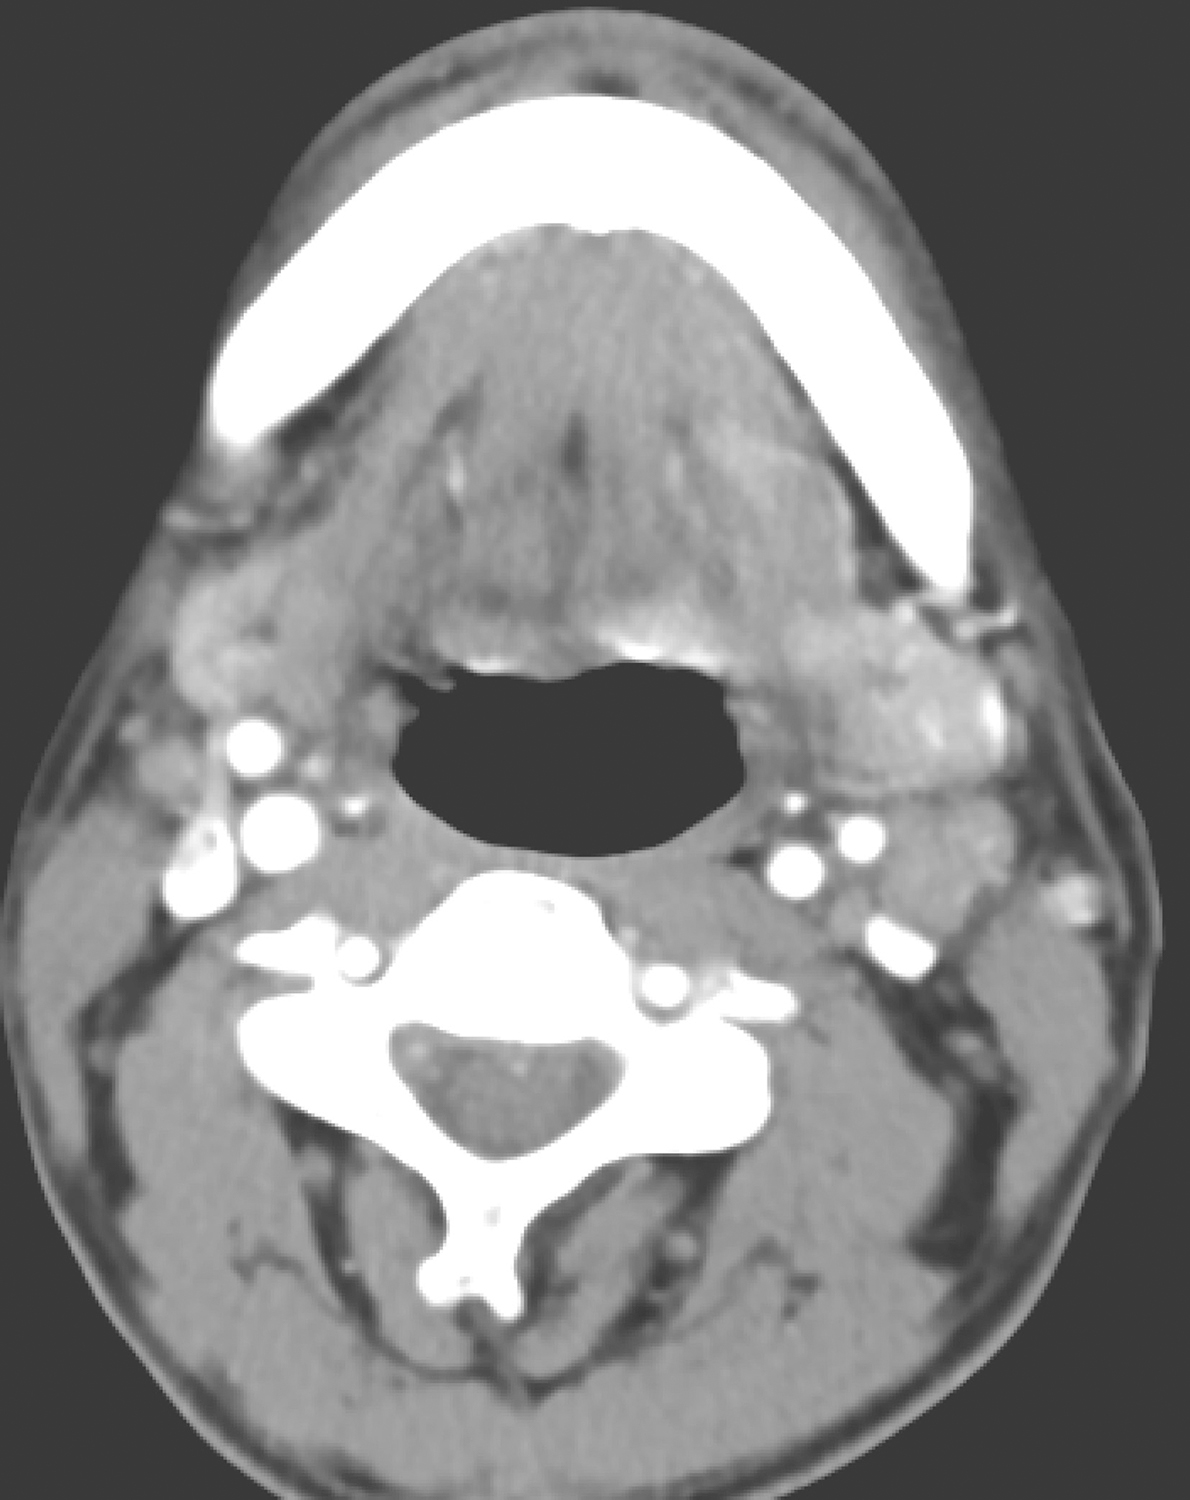

2.2014年11月2日电子鼻咽喉镜检查

鼻腔进镜顺利。鼻咽部表面光滑,略充血,未见明显异常。口咽双侧扁桃体未见肿大。左侧会厌谷及会厌舌面可见溃疡型肿物,左侧咽会厌皱襞受累及,邻近舌根部可疑侵及,向右侧侵犯超过中线位置,会厌左侧喉面及游离缘肿胀、明显增厚(图3)。左侧梨状窝未见明显侵及。下咽部基本平整。喉部双侧披裂对称,未见侵及。双侧声带和室带光滑,未见侵及。双侧声带活动正常。

内镜诊断:

左侧会厌谷及会厌舌面可见溃疡型肿物,符合恶性。

图3 左侧会厌谷及会厌舌面溃疡型肿物